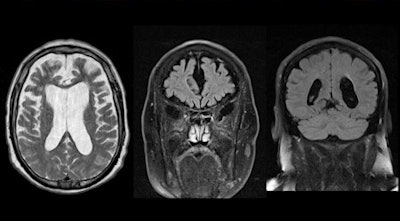

Typical example of a 73 year-old patient with fronto-temporo-lobar degeneration (FTLD). Note the apparent gradient of the atrophy from frontal to parieto-occipital, with marked widening of the sulci in the frontal lobes yet comparably minor widening of the sulci in the parieto-occipital region. Axial T2 and coronal fluid-attenuated inversion-recovery (FLAIR) in the frontal and parieto-occipital region. Image courtesy of Dr. Sven Haller.

Typical example of a 73 year-old patient with fronto-temporo-lobar degeneration (FTLD). Note the apparent gradient of the atrophy from frontal to parieto-occipital, with marked widening of the sulci in the frontal lobes yet comparably minor widening of the sulci in the parieto-occipital region. Axial T2 and coronal fluid-attenuated inversion-recovery (FLAIR) in the frontal and parieto-occipital region. Image courtesy of Dr. Sven Haller.Eventually, it may be possible to see what at the moment is still "invisible" during a primary radiological inspection because many forms of dementia have spatial atrophy patterns detectable on neuroimaging and advanced image analysis techniques can spot subtle anomalies, they added. Interindividual variation explains variable cognitive impairment despite the same degree of atrophy.